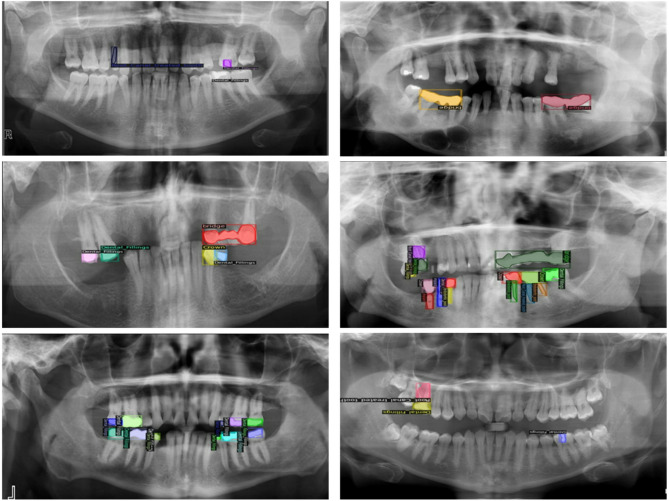

Data labelling

Annotation of the data set led to the proper training of YOLOv11, ViT, and Faster R-CNN, which resulted in the accurate interpretation and classification of dental radiographic images. Roboflow and CVAT are two different platforms that were used for the data annotation process. The annotation procedures required bounding boxes and polygons to surround target objects while preparing datasets that suited YOLOv11, Faster R-CNN, and ViT. Figure 2 displays the six annotated classes: crown, dental fillings, endodontic post, root canal-treated tooth, bridge, and implant. The detection performance required detailed labelling because dental structures have different levels of complexity and radiographic images show variable image quality.

Fig. 2.

Data annotation of different classes by using Roboflow